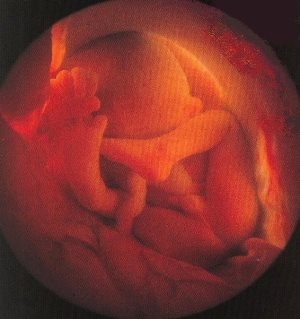

Фото плода на 28 неделе беременности (возраст плода 26 недель)

Изменения происходят и во внешнем виде малыша: на его ручках и ножках появляются перетяжки, щеки становятся более округлыми, а лицо выглядит менее сморщенным. Волосы начинают накапливать пигмент и постепенно темнеют, и у некоторых детей этот процесс происходит так быстро, что их волосы становятся темнее, чем предсказывают гены. Поэтому дети, рожденные от мам-блондинок на 28-й неделе, могут оказаться брюнетами. Кожа малыша по-прежнему имеет красноватый оттенок из-за близко расположенных капилляров.

На 28-й акушерской неделе у малыша уже практически полностью сформированы и функционируют органы, а также системы, отвечающие за регуляцию. Однако он все еще не полностью готов к жизни вне материнского организма.

На 28-й акушерской неделе длина плода составляет 36-38 см, его масса колеблется от 1200 до 1300 граммов. Обхват головы равен 70,5 мм, окружность грудной клетки – 71,9 мм, а окружность живота достигает 73,5 мм.